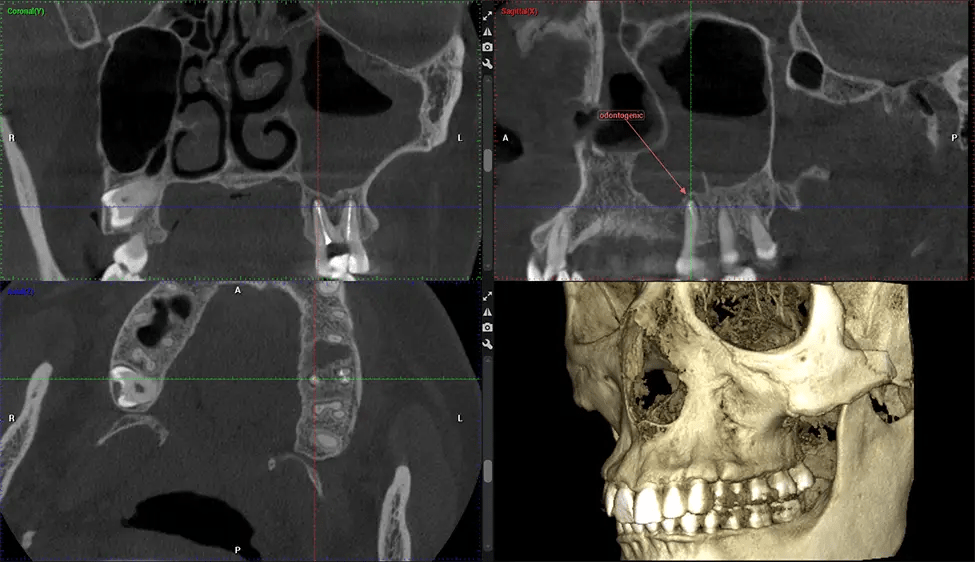

This 3D scan, called cone beam computed tomography, gives your dentist a more complete image of your oral anatomy and disease processes than a traditional X-ray. Unlike conventional X-rays, which capture a 2D image of your mouth from various angles, a 3D scan takes multiple digital X-rays for one image. It provides a complete view of your jaw, teeth, nerves, and soft tissues. This enhanced view allows dentists to detect minor issues not visible in traditional 2D scans, such as impacted wisdom teeth or bone fractures in the sinus cavity.

There are many benefits to using CBCT technology, especially compared to the traditional 2D X-ray format. One of the most significant advantages of CBCT scans is that they provide much more information than traditional X-rays. A scan lets your dentist see images from all angles of your jaw and mouth, including your sinuses, nasal cavity, cheekbones, and other surrounding areas. This added information helps your dentist craft a comprehensive treatment plan that addresses all aspects of your oral health.

Another significant benefit is that 3D imaging provides more precise images of your bone structure. These images are more detailed, providing you with a more accurate diagnosis. An accurate diagnosis means better treatment for you.

Planmeca Viso G7 CBCT ( Cone Beam CT Scan ) is designed to surpass the demands of industry leaders, specialists, and large institutions. It’s has a large ø25×30 cm sensor with four built-in cameras. It can capture unlimited volume sizes from a ø3×3 cm to a ø30x30cm volume capturing the skullcap through C7 on the cervical spine. The Planmeca Viso G7 offers the industry’s largest single volume scan of ø30×19 cm. It’s poised to handle advanced imaging modalities such as Planmeca ProFace® and Planmeca 4D™ Jaw Motion technology. The occipital head support allows an unimpeded view of facial tissue.

Planmeca is the only manufacturer clinically proven to dramatically reduce patient radiation without sacrificing image quality. Planmeca Ultra Low Dose™ achieves an average reduction in dose of 77% without a statistical reduction in image quality allowing doctors to incorporate 3D imaging into routine protocols with effective patient radiation often lower than 2D intraoral imaging. This increases patient care, allows doctors to diagnose more dentistry, and often earlier in disease progression, than with 2D imaging alone.